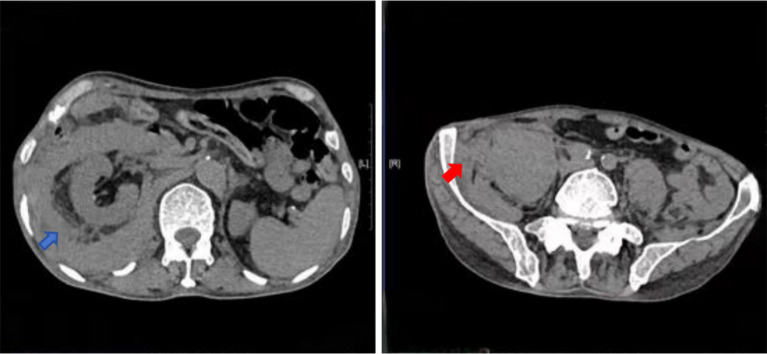

Transcatheter arterial embolization for retroperitoneal bleeding in patients with lumbar artery injury and essential thrombocythemia: a case description.